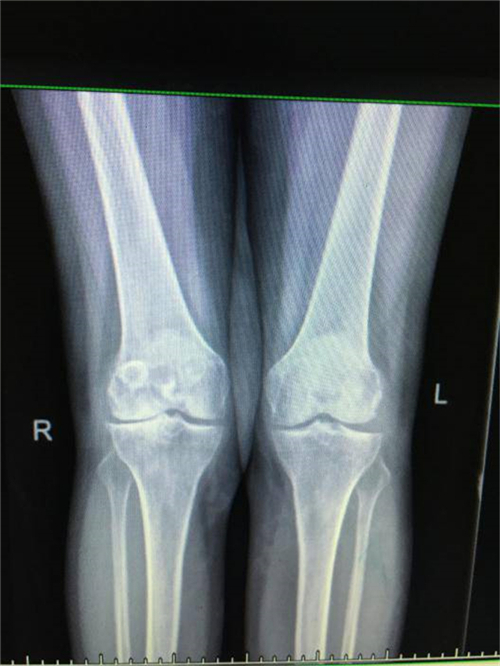

术前X线

得知郴州市第四人民医院骨科掌握了这一手术技术,便前来就诊。谭主任接诊到该患者后,对其进行了详细的体格检查,发现其左膝关节僵直,屈伸活动不能,负重时膝关节疼痛明显加重,膝关节X线片提示膝关节退变严重,关节间隙明显变窄,并有游离体形成,诊断为左膝关节重度骨关节炎并关节僵直,有明确的膝关节置换手术指征。